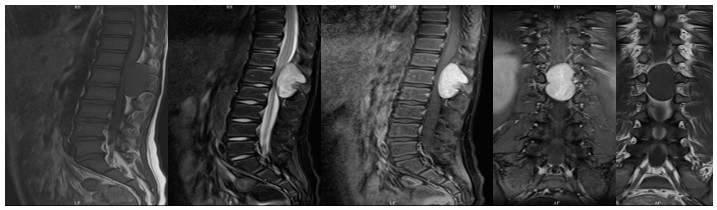

10歲小孩術(shù)前增強MR